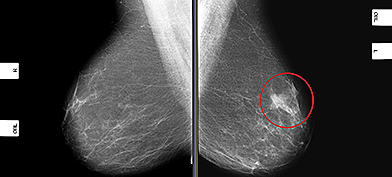

Mammograms

Knowing what to expect during a routine mammogram screening can ease first-timers’ stress.

As women get older, they may want to reassess how often they get mammogram screenings.